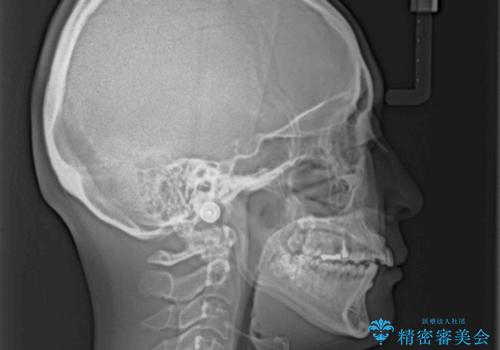

奥歯の咬み合わせは、上顎歯列が理想的な一よりも数mm前方にある状態でした。

なるべく早めに治療を終えたいとのことで、補助装置を用いて上顎臼歯を後方に移動させ、同時にワイヤー装置にて整えることとしました。